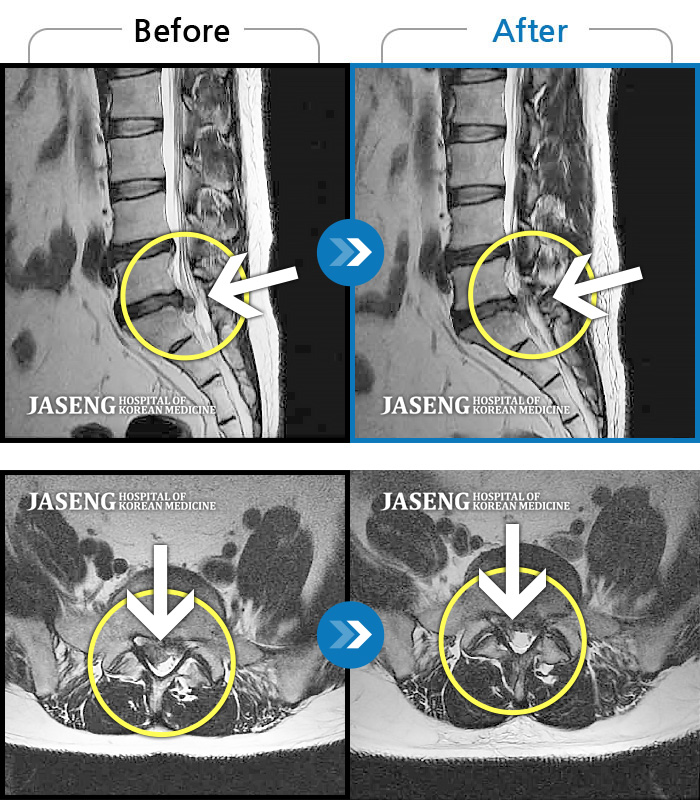

허리디스크

잠실 · 한상욱 원장

허리통증과 함께 좌측 엉치, 허벅지, 종아리 후면으로 저림이 심하여 걷기가 힘들어요.

촬영시기

2021.09.14 ~ 2022.05.14

2022.05.24